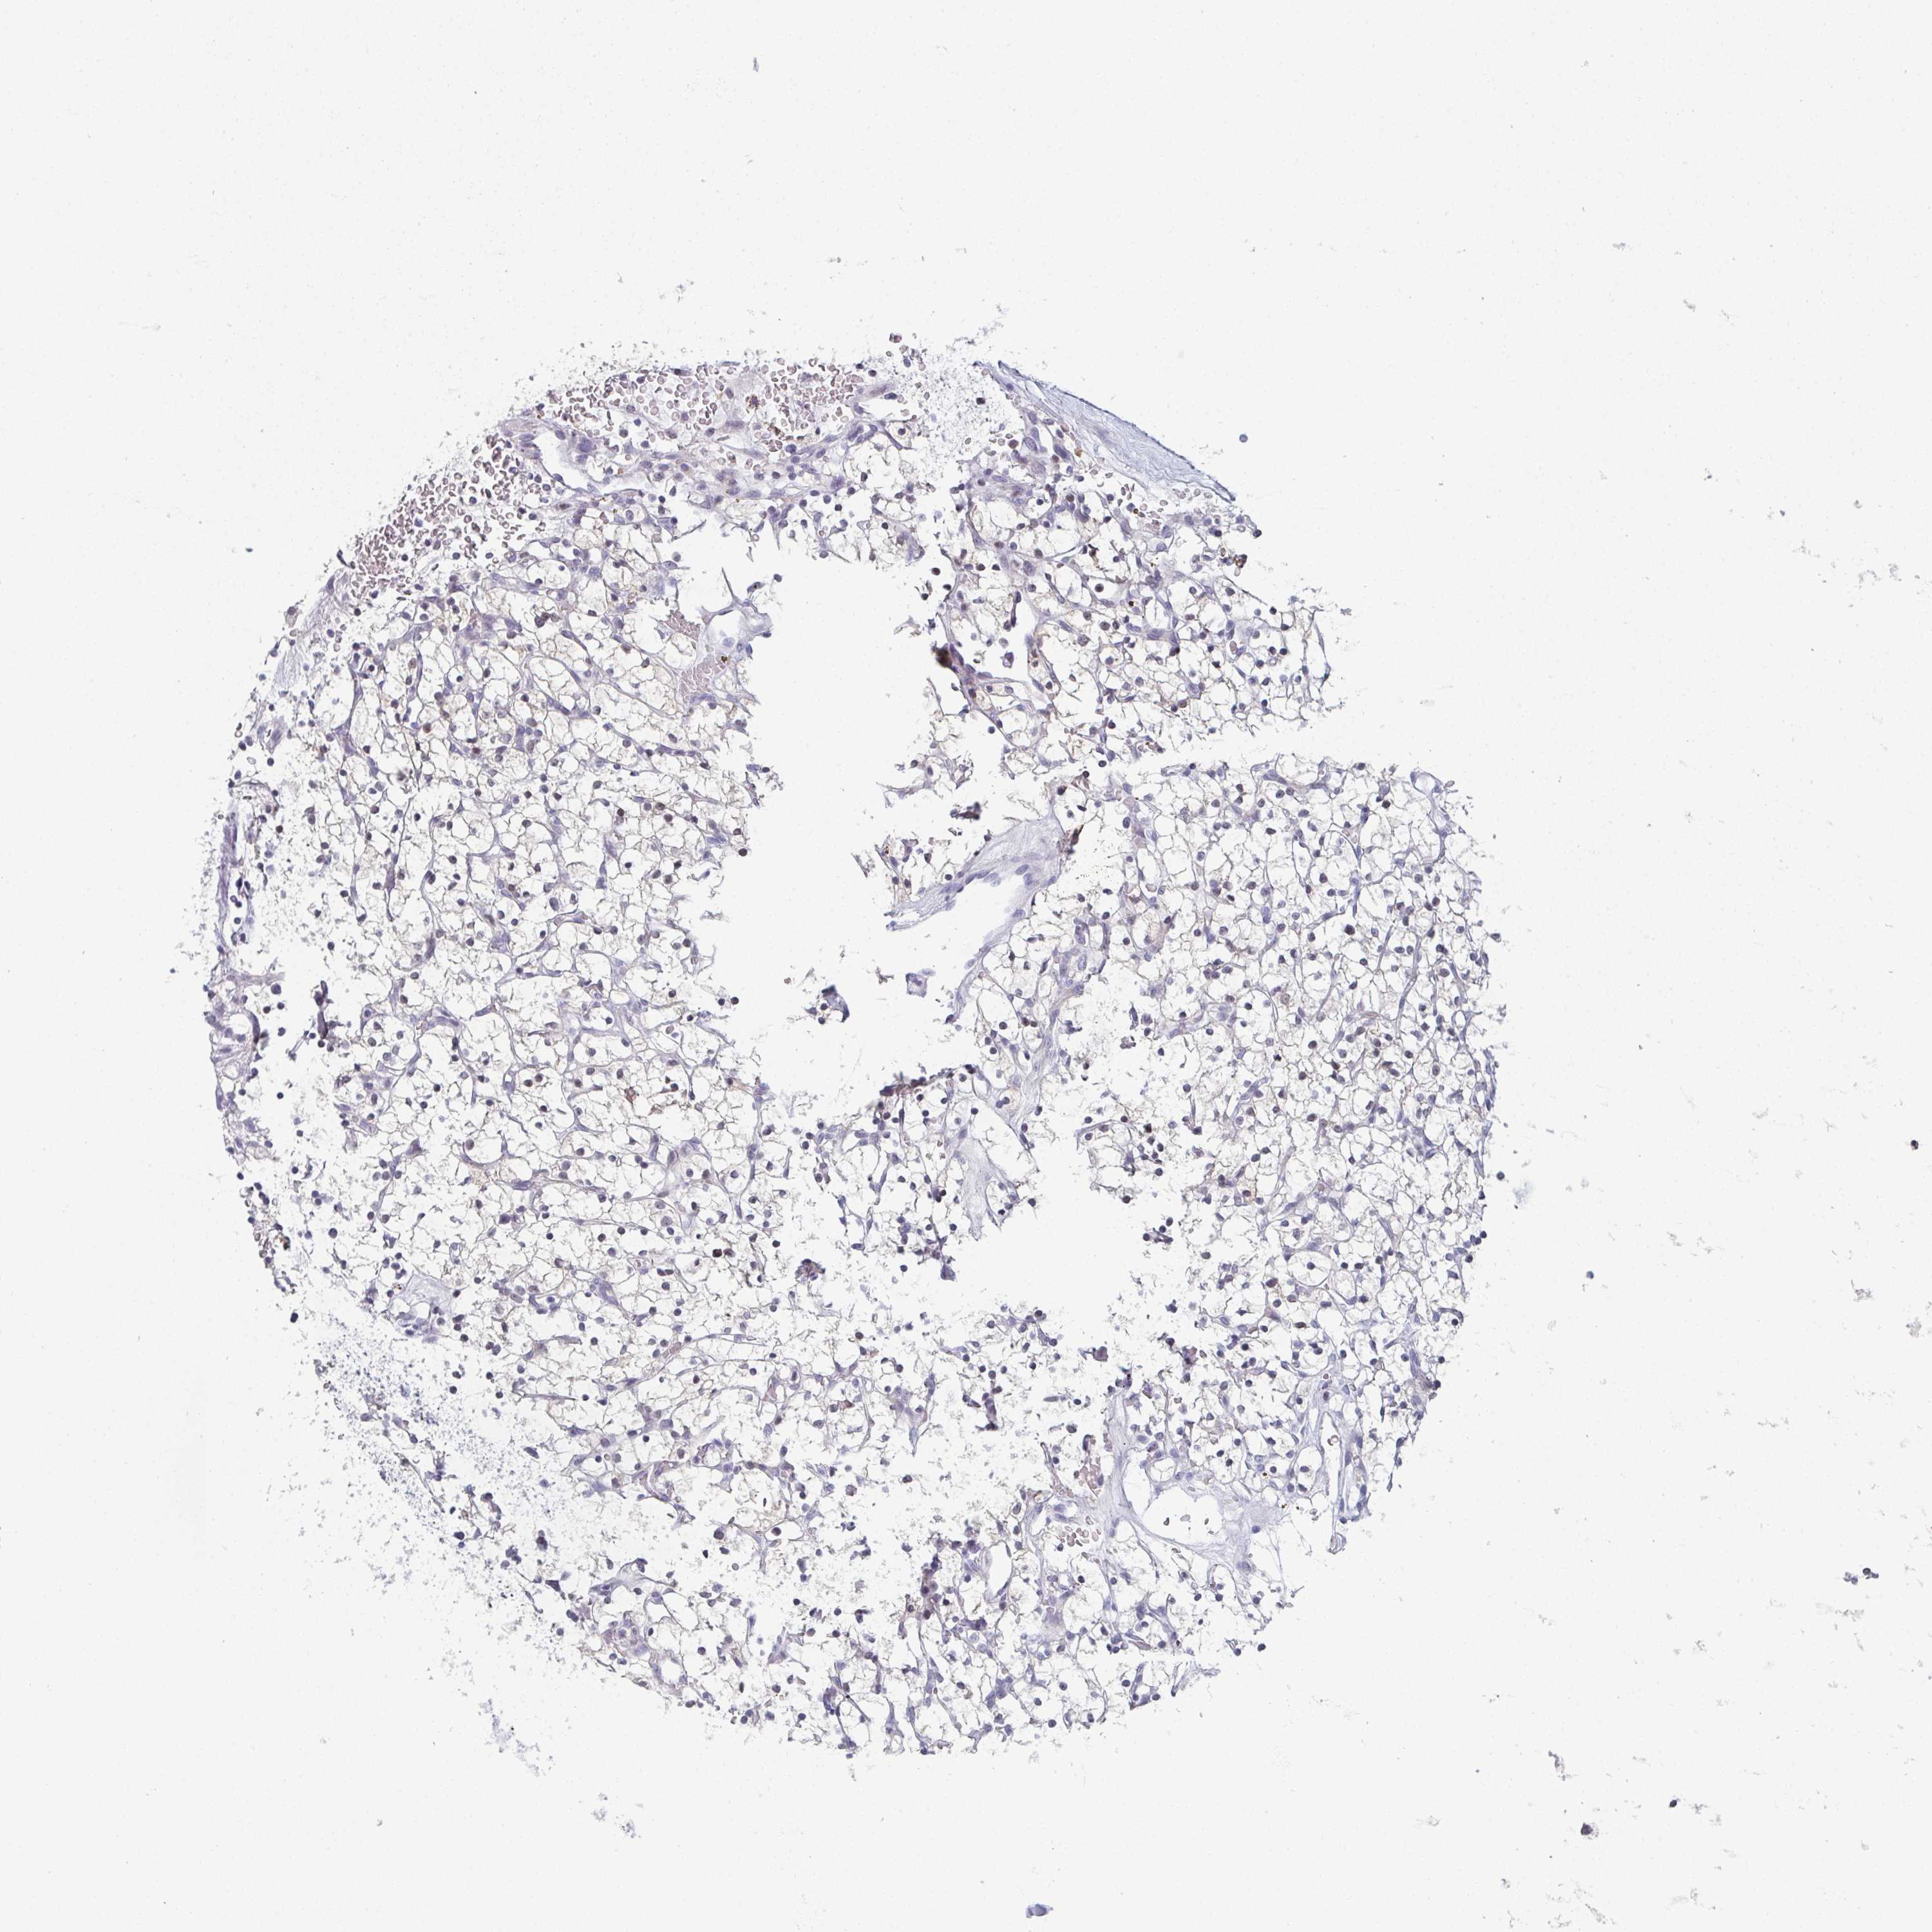

KIDNEY RENAL CLEAR CELL CARCINOMA (VALIDATION) - Interactive survival scatter ploti

The Survival Scatter plot shows the clinical status (i.e. dead or alive) for all individuals in the patient cohort, based on the same data that underlies the corresponding Kaplan-Meier plots. Patients that are alive at last time for follow-up are shown in blue and patients who have died during the study are shown in red.

The x-axis shows the expression levels (FPKM) of the investigated gene in the tumor tissue at the time of diagnosis. The y-axis shows the follow-up time after diagnosis (years). Both axes are complimented with kernel density curves demonstrating the data density over the axes. The top density plot shows the expression levels (FPKM) distribution among dead (red) and alive patients (blue). The right density plot shows the data density of the survived years of dead patients with high and low expression levels respectively, stratified using the cutoff indicated by the vertical dashed line through the Survival Scatter plot. This cutoff is automatically defined based on the FPKM cutoff that minimizes the p-score. The cutoff can be changed by dragging the vertical line or by entering a cutoff value in the square labeled "Current cut-off".

Under the Survival Scatter plot the p-score landscape (black curve; left axis) is shown together with dead median separation (red curve; right axis). Dead median separation is the difference in median mRNA expression between patients who have died with high and low expression, respectively. It is calculated as follows: median FPKM expression of dead patients with high expression - median FPKM expression of dead patients with low expression. This is intended to aid the user in visually exploring custom cutoffs and the associated p-scores and dead median separation.

Individual patient data is displayed and can be filtered by clicking on one or more of the category buttons on the top of the page. Categories describing expression level and patient information include: high, low, alive, dead, female, male and tumor stages. The scale of the x-axis can be toggled between linear and log-scale by clicking on the "x log" button. Mouse-over function shows TCGA ID, patient information and mRNA expression (FPKM) for each patient.

& Survival analysisi

Kaplan-Meier plots summarize results from analysis of correlation between mRNA expression level and patient survival. Patients were divided based on level of expression into one of the two groups "low" (under cut off) or "high" (over cut off). X-axis shows time for survival (years) and y-axis shows the probability of survival, where 1.0 corresponds to 100 percent.

PYCR3 is not prognostic in Kidney Renal Clear Cell Carcinoma (validation)

Best expression cut offi

Based on the FPKM value of each gene, patients were classified into two groups and association between prognosis (survival) and gene expression (FPKM) was examined. The best expression cut-off refers the FPKM value that yields maximal difference with regard to survival between the two groups at the lowest log-rank P-value. Best expression cut-off was selected based on survival analysis .

When clicking on this number, the vertical dashed line indicating cut-off, the interactive survival plot, and the Kaplan-Meier curve will be adjusted to show results based on the best expression cut-off.

: 0.86

TCGA RNA samplesi

RNA-seq data is reported as average FPKM (number Fragments Per Kilobase of exon per Million reads), generated by the The Cancer Genome Atlas (TCGA) .

Normal distribution across the dataset is visualized with box plots, shown as median and 25th and 75th percentiles. Points are displayed as outliers if they are above or below 1.5 times the interquartile range. FPKM values of the individual samples are presented next to the box plot.

Average pTPM 1.1

Number of samples 100